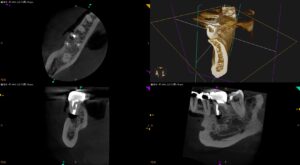

紹介患者さんの治療。 主訴は 右下治療した奥歯の歯茎が腫れた である。 歯内療法学的検査(2025.8.8) PA(2025.8.8) CBCT(2025.8.8) MB ML D Radix 歯内療法学的診断(2025 … 続きを読む 右下治療した奥歯の歯茎が腫れた…〜右下臼歯の歯根端切除術はなぜ難しいのか? #30 M Apicoectomy